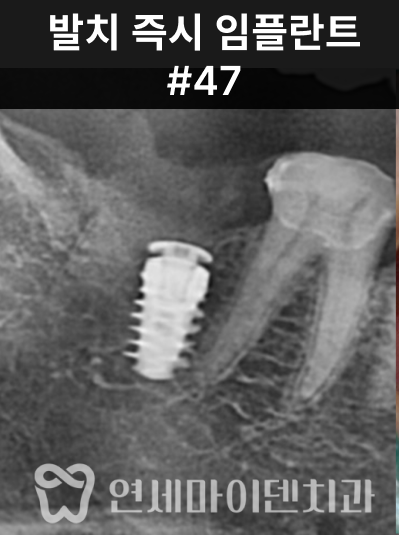

결국 보존 불가로 판단했습니다.

이에 따라 발치 후 즉시 임플란트를 진행했습니다.

다행히 치조골 상태가 양호해 즉시 식립이 가능했습니다.

임플란트 식립 후 골이식과 멤브레인 적용을 통해 뼈의 안정화를 유도했고,

2주 뒤 봉합사 제거 후 출국하실 수 있도록 계획했습니다.

최종 보철물은 귀국 시기에 맞춰 맞춤 제작하여 완성했습니다.